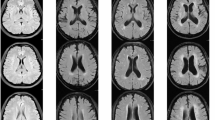

Eccentricity was chosen to test as a WMH shape feature for the between group comparisons, because it is translation-, scale- and rotation-invariant, has a relatively small skewness, does not show a ceiling effect in our measurements, has a limited floor effect (a perfect sphere) and is easy to comprehend and link to visual observations of WMH shape. An example of the WMH shape feature eccentricity for a punctuate deep WMH is shown in Fig. 1. A low eccentricity means close to spherical and a high eccentricity means strongly ellipsoidal. As can be appreciated from the figure, this difference in WMH shape can also be perceived visually.

Two WMH with a different eccentricity value. This figure represents two WMH that have a different eccentricity value. The shown FLAIR images have a voxel size of 0.96 × 0.96 × 3.00 mm3. The left panels show a punctuate deep WMH with a low eccentricity of 1.0 (close to spherical), which is seen in only one slice. The right panels show a punctuate deep WMH with a high eccentricity of 4.2 (strongly ellipsoidal), which is caused by the lesion extending in multiple slices. As can be appreciated, this difference in WMH shape can also be perceived visually.